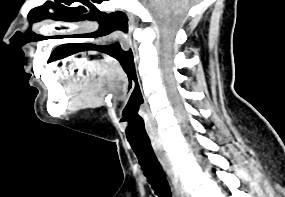

Оптимальным методом обследования гортани и голосовых связок является мультиспиральная компьютерная томография. Метод позволяет подробно визуализировать состояние данной анатомической области и выявить патологические изменения, которые незаметны при ларингоскопии (визуальный осмотр гортани с помощью специальных инструментов), проведении УЗИ и обычной рентгенографии.

Компьютерная томография особенно полезна для оценки состояния хрящей гортани, которые лучше всего визуализируются с помощью данного исследования. В частности, мультиспиральная КТ позволяет выявить распространение рака гортани в ткань щитовидного хряща и другие окружающие структуры.

На полученных снимках можно оценить состояние всех структурных элементов гортани, голосовых складок, хрящей, а также лимфатических узлов, сосудов и шейных позвонков на исследуемом уровне. Инновационные возможности аппарата позволяют построить 3D-модель зоны исследования, которая дает наглядную картину пространственного расположения органов, что бывает особенно важно при планировании хирургических операций.